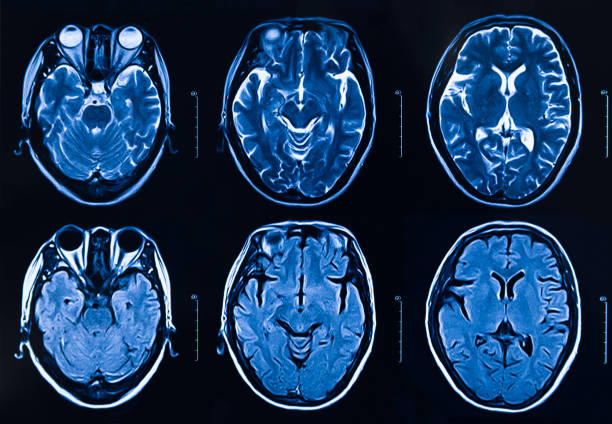

本研究納入2018年1月1日至2020年10月31日發病168小時內發生急性ICH的患者。間充質干細胞被靜脈注射給9名患者(5名女性,4名男性),平均年齡(范圍)為61(36-84)歲。表1總結了人口統計學和臨床??特征 。出于描述目的,患者按照入組順序獲得編號,并連續分配到三組中的一組,每組三人。根據模型 2 分割,ICH體積范圍為0.1至54.9mL(平均ICH體積為23.5mL)。5例ICH累及局部腦葉,其余則位于基底節或外囊深處。在三名患者中,ICH位于丘腦(圖1),在一名患者中,血腫位于多個腦結構(即尾狀核、殼核和蒼白球)。平均而言,MSC在ICH后3天進行注射。